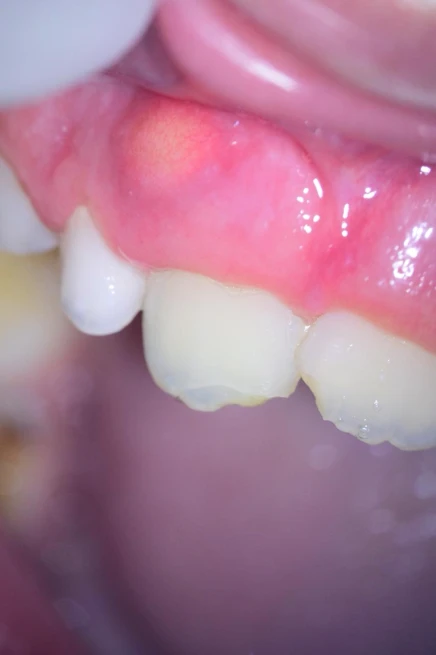

Após uma semana e regressão total da fístula (figura 4), foi realizada uma irrigação com hipoclorito de sódio 2,5% com PUI e irrigação final com soro fisiológico. Além disso, foi feita a sucção com uma cânula aspiradora (Capillary Tips da Ultradent) e um único cone de papel (não deixar molhado).